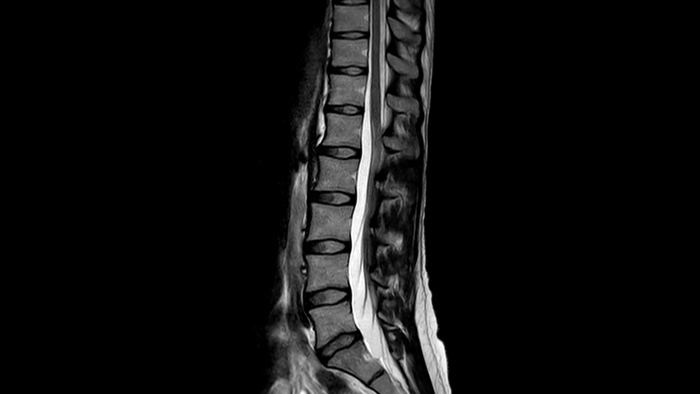

確信が持てる画像診断 同じスキャン時間で、空間分解能を最大65%向上⁴

確信が持てる画像診断 すべての臨床領域でイメージング機能を拡張します。医療従事者が享受できるメリットをご覧ください。

1 稀なケースとして、マグネットの密封が損なわれた場合でもヘリウムの量はわずかであるため、漏れたヘリウムが室内の酸素レベルに影響を与えることは実質的にありません。 2 Philips SENSEとの比較。 3 心拍数が低い (50 bpm) とき。Compressed SENSEなしのフィリップススキャンと比較した場合。 4 等方性3D MSK VIEWスキャンで、Compressed SENSEなしのフィリップススキャンと比較した場合。